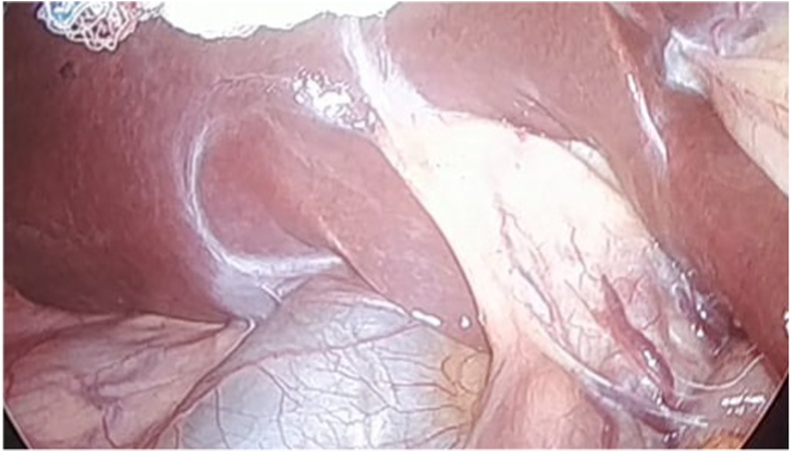

During laparoscopy, the liver and duodenum appeared normal without adhesions, yet the gallbladder was nowhere to be seen. The bile ducts were recognized, and after a thorough examination of the abdominal cavity, the gallbladder was not identified; therefore, the procedure was concluded to avoid any injury (Fig. 2A, Fig. 2BA and B).

Fig. 2A.

Transoperative view of the left and right hepatic ducts.

Fig. 2B.

Transoperatvie view of absence of gallbladder.